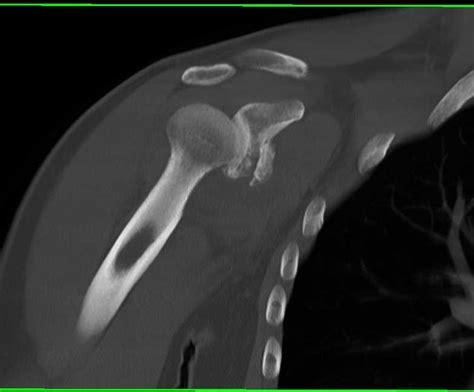

Arthroscopic reduction and internal fixation of an anterior glenoid fracture. Glenoid fractures are uncommon, accounting for ~10% of scapular fractures.

An extremely rare type of fracture, glenoid fossa fractures require a great amount of. Classification of glenoid cavity fractures: Glenoid fractures are uncommon, accounting for ~10% of scapular fractures.

The second most common glenoid fracture, glenoid fossa fractures, occur in extreme trauma cases to the shoulder.

Fractures to the glenoid are often seen in association with various shoulder instability patterns, although isolated fracture can occur less commonly following direct axial loading forces to the. Glenoid fractures are uncommon, accounting for ~10% of scapular fractures. The avulsions and rim fractures are strongly associated with anterior. Shoulder socket fracture or glenoid fracture is a specialty at florida orthopaedic institute. Ideberg classification of glenoid fracture. Classification of glenoid cavity fractures: Look for associated ac joint separation or clavicle fracture. The glenoid cavity can be described as an irregularly shaped oval, much like an inverted comma. These are typically high enegery injuries, assessment should begins with the a,b,c's. Horizontal split of scapula c. Displaced and compromises the subacromial space. There are two main causes of glenoid fractures, shoulder dislocation and impact. The glenoid is also tilted from superomedial to inferolateral by an average of 15 degrees. Arthroscopic reduction and internal fixation of an anterior glenoid fracture. Glenoid fractures are unusual injuries where the socket of the shoulder is damaged. The second most common glenoid fracture, glenoid fossa fractures, occur in extreme trauma cases to the shoulder. Fracture line through glenoid fossa exiting scapula laterally.